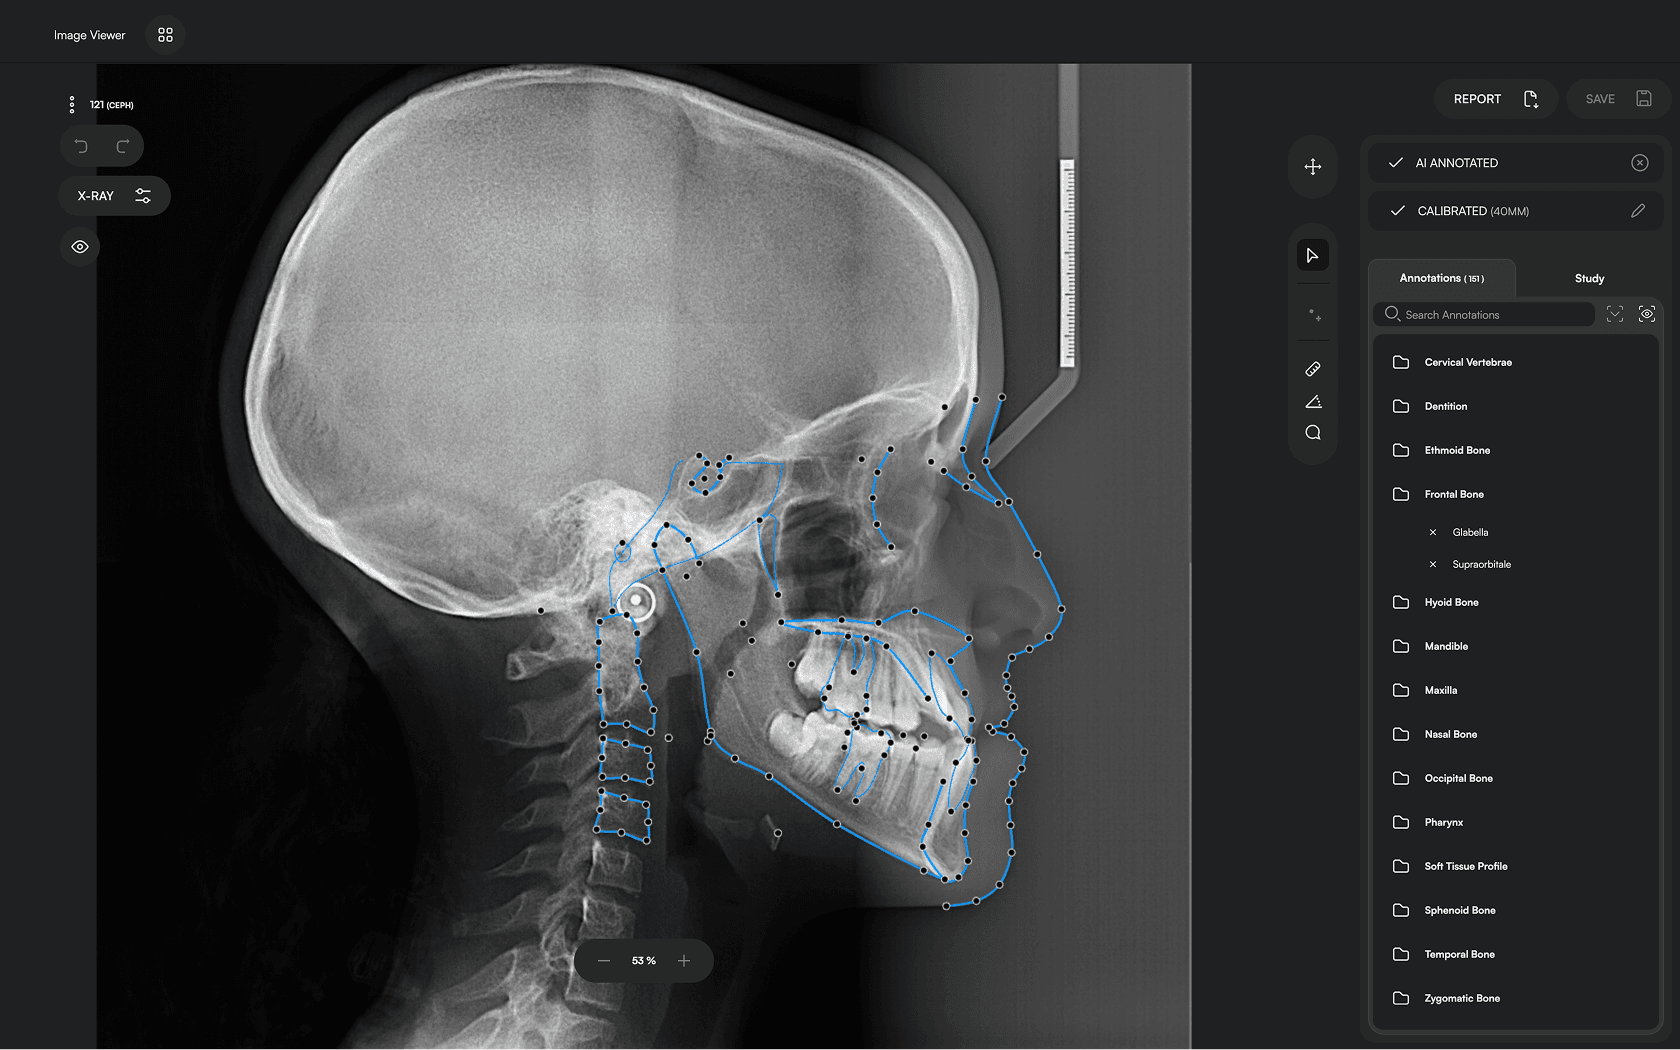

Diverse Analysis

Access automated studies like Steiner and Jefferson to assist in clinical assessment and enhance case evaluations.

Powerful Insights

Experience a comprehensive assessment of skeletal, dental, and soft tissue discrepancies.

Trace 150+ landmarks

Access 10 analyses

One-click reporting